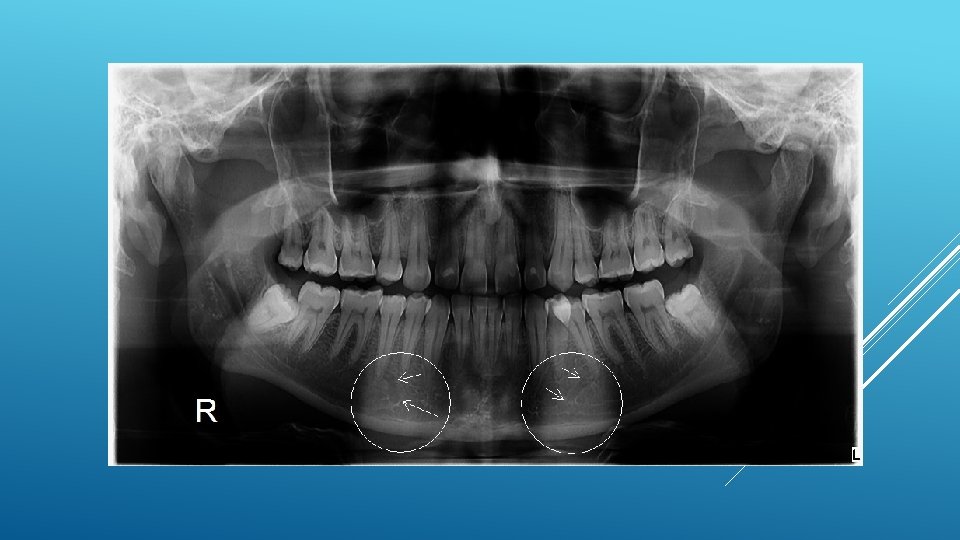

LOCATION AND DIMENSIONS OF THE MENTAL FORAMEN: A RADIOGRAPHIC ANALYSIS BY USING CONE-BEAM COMPUTED TOMOGRAPHY The majority of MF (56%) were located apically between the 2 premolars, and another 35. 7% of MF were positioned below the second premolar. On average, the MF was localized 5. 0 mm from the closest root of the adjacent tooth (range, 0. 3 -9. 8 mm). The mean size of the MF showed a height of 3. 0 mm and a length of 3. 2 mm; however, individual cases showed large differences in height (1. 8 -5. 1 mm) and in length (1. 8 -5. 5 mm). All mental canals exiting the MF demonstrated an upward course in the coronal plane, with 70. 1% of the mental canal presenting an anterior loop (AL) in the axial view. The mean extension of AL in cases with an AL was 2. 3 mm.

RELATIONSHIP BETWEEN THE POSITION OF THE MENTAL FORAMEN AND THE ANTERIOR LOOP OF THE INFERIOR ALVEOLAR NERVE AS DETERMINED BY CONE BEAM COMPUTED TOMOGRAPHY COMBINED WITH MIMICS The parameters were measured, and their values include mean (SD) anterior loop length, 1. 16 (1. 78) mm; anterior loop angle, 19. 13 (26. 89) degrees; inferior alveolar canal diameter, 3. 01 (0. 67) mm; height of the inferior alveolar canal, 10. 32 (1. 56) mm; 2 -dimensional mental foramen diameter, 2. 97 (0. 61) mm; 3 D mental foramen diameter, 2. 95 (0. 59) mm; 2 -dimensional vertical height of the mental foramen, 14. 67 (1. 67) mm; and 3 D vertical height of the mental foramen, 14. 61 (1. 69) mm. The mental foramen was located apically between the first and second premolars in 51. 67% and below the second premolar in 40. 83% of the cases.

THE MENTAL FORAMEN OR "THE CROSSROADS OF THE MANDIBLE. " AN ANATOMIC AND CLINICAL OBSERVATION] [ARTICLE IN FRENCH, GERMAN] THOMAS VON ARX 1 This paper presents a clinical and anatomical review of the mental foramen (MF) based on recent publications (since 1990). Usually, the MF is located below the 2 nd premolar or between the two premolars, but it may also be positioned below the 1 st premolar or below the mesial root of the 1 st molar. At the level of the MF, lingual canals may join the mandibular canal (hence the term "crossroads"). Accessory MF are frequently described in the literature with large ethnic variations in incidence. The emergence pattern of the mental canal usually has an upward and posterior direction. The presence and extent of an "anterior loop" of the mental canal may be overestimated with panoramic radiography. Limited cone-beam computed tomography currently appears to be the most precise radiographic technique for assessment of the "anterior loop". The mental nerve exiting the MF usually has three to four branches for innervation of the soft tissues of the chin, lower lip, facial gingiva and mucosa in the anterior mandible. The clinician is advised to observe a safety distance when performing incisions and osteotomies in the vicinity of the MF.

ANATOMICAL RELATIONSHIP BETWEEN MENTAL FORAMEN, MANDIBULAR TEETH AND RISK OF NERVE INJURY WITH ENDODONTIC TREATMENT he root apex of the mandibular second premolar (70 %), followed by the first premolar (18 %) and then the first molar (12 %), was the closest to the MF. Ninetysix percent of root apices evaluated were >3 mm from the MF. An AL was present in 88 % of the cases. Conclusions: With regards to endodontic treatment, the risk of nerve injury in the vicinity of the MF would appear to be low. However, the high incidence of the AL highlights the need for clinicians to be aware and careful of this important anatomical feature.

ASSESSMENT OF MORPHOLOGICAL AND ANATOMICAL CHARACTERISTICS OF MENTAL FORAMEN USING CONE BEAM COMPUTED TOMOGRAPHY All mental foramina were visualized. Regarding location, 49. 2% of the MFs were located between first and second premolars, 7. 7 distal and 39. 7% coincident to the apex of the mandibular second premolar. The mean MF opening angle was 45. 4° on the right side, and 45. 9° on the left. There were no statistically differences between gender groups with regard to the opening angle degree